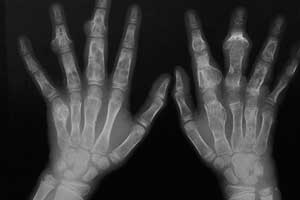

- рентгенографии — обязательное обследование, с помощью которого выявляется опухоль и описываются ее основные признаки, однако для постановки окончательного диагноза необходимо лабораторное исследование тканей, полученных при биопсии;